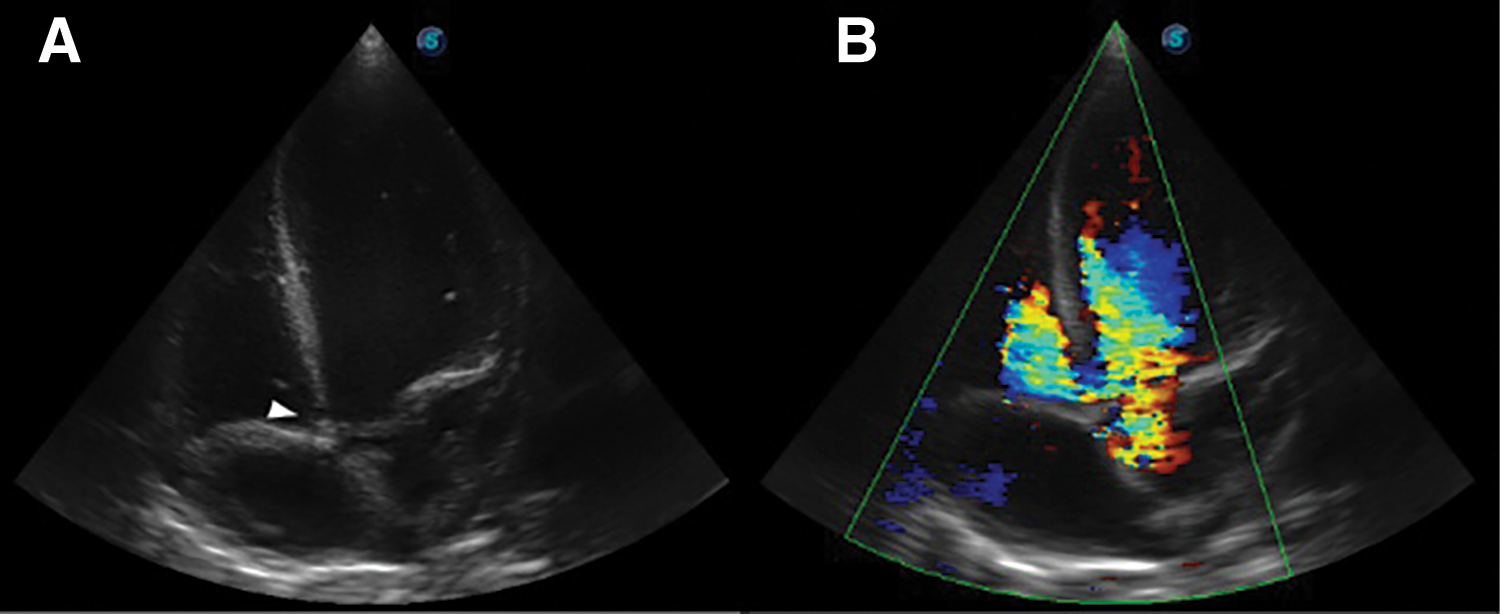

Further review and meticulous physical examination and investigations revealed confused and restless patient, febrile (T = 40°C), pale, acyanosed, RR: 38 breaths/min, SPO2 90%, pulse rate 122/min, blood pressure of 120/40 mmHg, Jugular venous pressure not raised, displaced apex and hyperdynamic, heart sound: S1, S2 and S3 gallop, PSM grade 3/6 loudest at 4th left intercostals space lateral to sternal border, tricuspid PSM grade 1/6 epigastrium, aortic diastolic murmur grade 2/4, bi-basal fine crackles. a provisional diagnosis of congenital heart disease (VSD) with aortic incompetence complicated by infective endocarditis, sepsis, AKI and acute left ventricular HF was entertained with differential diagnosis of Rheumatic heart disease (RHD) with complications. He was started on oxygen therapy and switched from generic ceftriaxone to the branded ceftriaxone (Rocephin). Metronidazole was stopped and gentamicin added adjusted for renal function, he also received furosemide along with conservative renal therapy and close monitoring. Additional relevant investigations were requested which include (1) Laboratory test as indicated in (Table 1b) (2) Electrocardiogram (ECG) which showed sinus tachycardia with heart rate of 115 beat per min (Fig. 1). (3) Chest X-ray (CXR): Showed cardiomegaly of biventricular configuration with cardiothoracic ratio of 0.61, prominent pulmonary vasculature, upward blood diversion and blunted left costophrenic angle (Fig. 2). (4) Transthoracic echocardiography (TTE): revealed interventricular septal thickness of 9.4 mm and left ventricular posterior wall thickness of 13.5 mm. Moderately dilated left ventricle (LV) with internal diameter of 66.4 mm, mildly dilated left atrial with internal of diameter 44.1 mm, mildly dilated right ventricle with internal diameter of 43.9 mm, moderately dilated right atrium with internal diameter of 53.2 mm, Peri-membranous VSD measured 5.3 mm in size with color Doppler demonstrating left to right shunt (Fig. 3A,B). Aortic valve prolapse of the non-coronary cusp 4.5 mm from the plane and severe aortic regurgitation [Width of vena contracta of 7.4 mm and regurgitant jet width/LV out flow tract diameter ratio of 2.1 cm/2.6 cm of 0.80 (80%)] (Fig. 4A,B), large oscillating echogenic mass attached to tricuspid valve leaflet was noted (Fig. 5) and (Supplementary Materials Video S1). LV Ejection fraction (EF) was 64.7% on M-mode guided 2-D with fractional shortening of 36.3% and normal RV systolic function (TAPSE: 20.4 mm). LV end-diastolic volume index was 135.8 mL/m2 (Severely abnormal), while LV end-systolic volume index was 47.9 mL/m2 (Severely abnormal) and LV mass index (LVMI) was 209.3 g/m2 (Severely abnormal). Other heart valves appeared normal in motion and morphology. Moderate mitral regurgitation, severe tricuspid regurgitation and mild pulmonary regurgitation were noted. Pulmonary arterial systolic pressure at rest was 52.2 mmHg.

Figure 3: TTE apical 5-chamber view, (A): Arrow head showing Peri-membranous VSD and (B): Color Doppler demonstrating left to right shunt